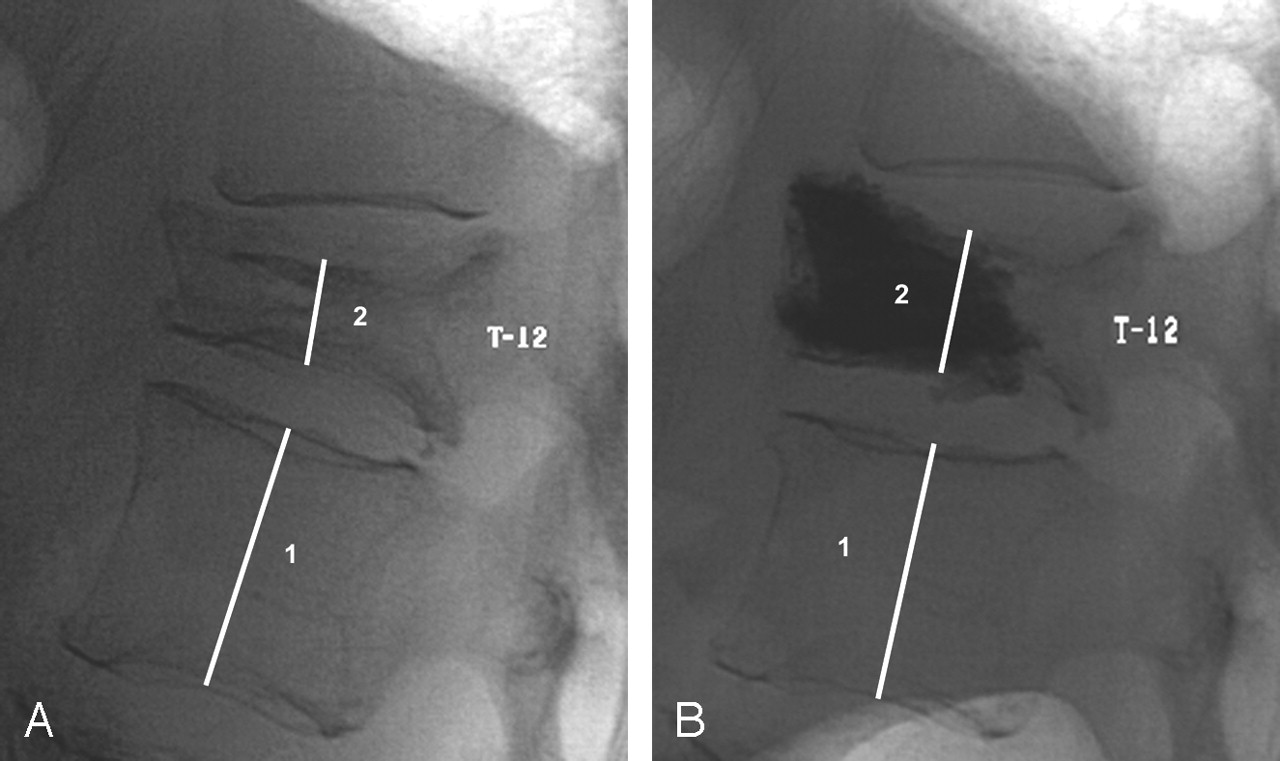

Osteoporosis is characterised by thin, fragile bones. Osteoporotic vertebral compression fractures are minimal trauma fractures of the vertebral (spine) bones (vertebrae). They can cause severe pain and disability. Vertebroplasty involves injecting medical-grade cement into a fractured vertebra through a needle inserted into the skin, under light sedation or general anaesthesia. The cement hardens in the bone space to form an internal cast.